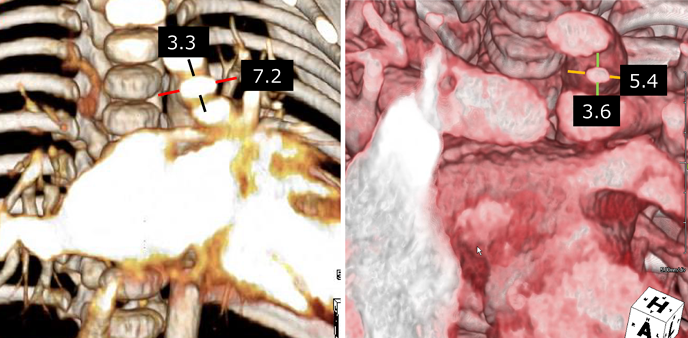

PDAの形態・サイズ測定は,通常側面像か左前斜位で判定される.しかし,CTでPDAの長軸方向に垂直な断面をみると,正円ではなく楕円形で横に長い(Fig. 2).したがって,縦径が同じでも横径によって脱落,遺残短絡,必要なコイルの本数は違ってくる.われわれはコイル閉鎖に限らず,乳児期にPDAのデバイス閉鎖が必要となる場合,CT検査によるPDA断面チェックをルーチンにしている.

Fig. 2 Cross section of the PDA at the narrowest portion

2-1) Type C PDA of 1 month old girl showed that the cross section of the PDA is ovale shaped with the longer diameter 7.2 mm and shorter one 3.3 mm. 2-2) Type C PDA of 1 year old girl. The cross section of the PDA is ovale shaped and the longer diameter is 5.4 mm and shorter one 3.6 mm. PDA, patent ductus arteriosus